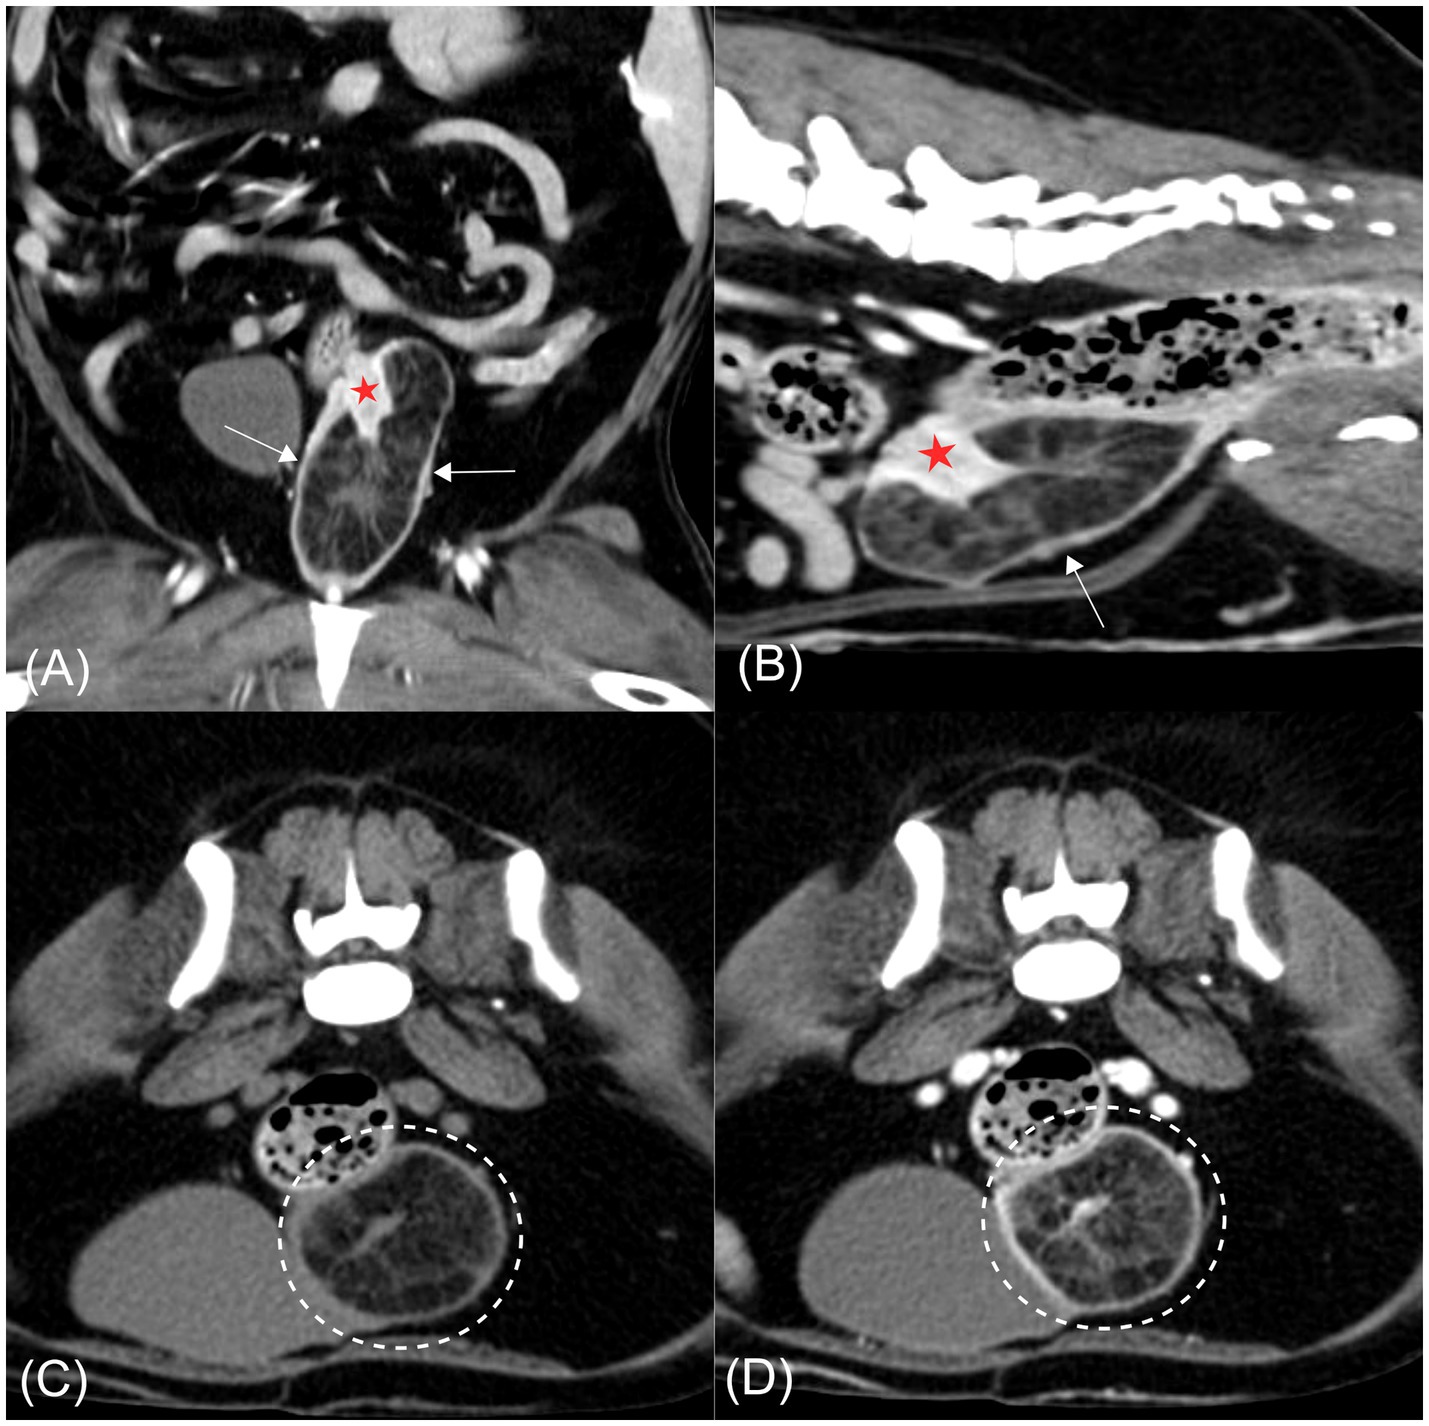

CT imaging revealed a well-defined hypoattenuating mass measuring approximately 37 × 35 × 73 mm, containing intraluminal soft tissue–attenuating striations, anatomically located at the level of the cervix and extending partially into the cranial vagina. The cervix appeared partially invaginated into the hypodense mass, with internal striations continuous with cervical tissue (Figures 2A,B). The invaginated cervical wall exhibited mild thickening and marked contrast enhancement relative to the vagina, aiding its radiological identification (19). Previous studies have reported that the cervix demonstrates a higher degree of contrast enhancement, reflected by higher attenuation values, than the vagina (19). In the present case, the conspicuous enhancement of the invaginated cervical wall was consistent with these findings (cervix, mean 183 HU; vagina, mean 160 HU), supporting the conclusion that the mass originated from the cervix rather than the vagina. Mild wall thickening and multiple small cystic lesions were also noted within the uterine horns and cervix. Both ovaries appeared unremarkable. The cervix showed mean attenuation values of 50 and 184 Hounsfield units (HU) on pre- and post-contrast CT images, respectively, consistent with soft tissue attenuation. The striated tissue contiguous with the cervix demonstrated HU values of 23 pre-contrast and 63 post-contrast, which fall within the range of soft tissue attenuation. In contrast, the hypoattenuating areas within the mass exhibited HU values of −113 pre-contrast and −90 post-contrast, consistent with fat attenuation (Figures 2C,D) (20).

Figure 2. Computed tomography images of a hyperplastic cervical polyp with lipomatous differentiation in a dog. (A) Post-contrast coronal image. (B) Post-contrast sagittal image. (C) Pre-contrast transverse image. (D) Post-contrast transverse image. A well-defined hypoattenuating mass is evident at the level of the cervix, partially extending into the cranial vagina (arrow). The mass contains intraluminal soft tissue-attenuating striations continuous with the partially invaginated and contrast-enhancing cervical wall (red asterisk). In both transverse images (C,D), hypoattenuating regions within the mass are consistent with fat attenuation and remain non-enhancing following contrast administration (dashed circle).